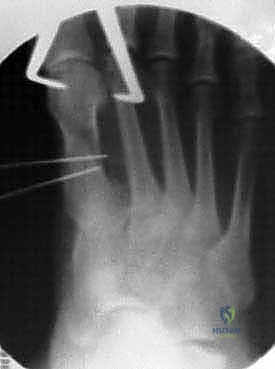

الخطوة الرابعة: إعادة التوجيه والتثبيت الداخلي

بعد قص العظم، يتم تحريك الجزء البعيد (الذي يحمل المفصل والإصبع) نحو الخارج لتصحيح التشوه وتضييق المسافة بين الأمشاط. بمجرد الوصول للوضع المثالي، يتم تثبيت العظمين معاً بقوة باستخدام برغيين أو ثلاثة من التيتانيوم الطبي عالي الجودة. هذه البراغي تدفن داخل العظم ولا تحتاج للإزالة لاحقاً.

الخطوة الخامسة: الإغلاق التجميلي

بعد التأكد من استقرار العظم ووضعه المثالي (غالباً باستخدام جهاز أشعة سينية داخل غرف العمليات Fluoroscopy)، يتم إزالة النتوء العظمي المتبقي. أخيراً، تُغلق الكبسولة المفصلية والجلد بخياطة تجميلية دقيقة لتقليل الندبات، وتوضع ضمادات ضاغطة خاصة.